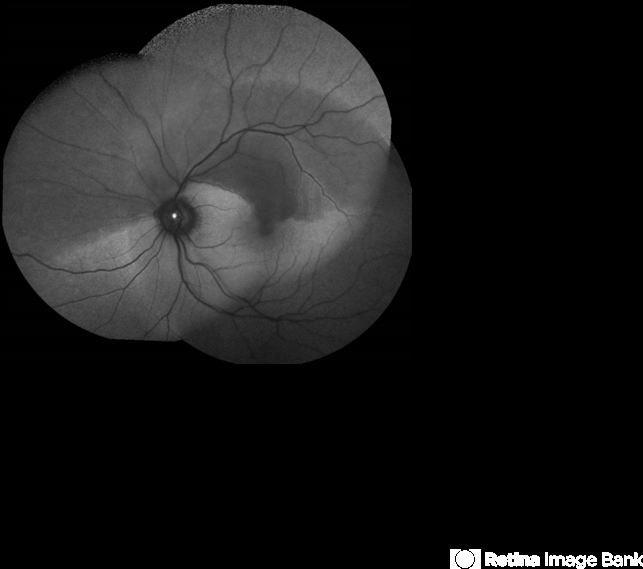

- Branch Retinal Artery Occlusion

- branch retinal artery occlusion (BRAO), embolus, retinal edema, fundus autofluorescence (FAF)

- Acute branch retinal artery occlusion with a calcium embolus at the disc which is hyper autofluorescent in fundus autofluorescence Imaging (FAF) -resembles an LED light source ('LED sign').